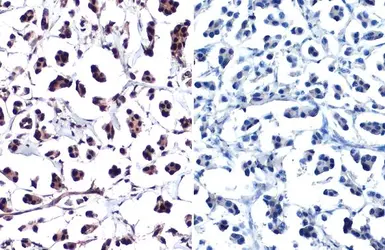

Anti-Histone H2A.XS139ph (phospho Ser139) antibody used in IHC (Paraffin sections) (IHC-P). GTX127342

GTX127342 IHC-P Image

Histone H2A.XS139ph (phospho Ser139) antibody detects Histone H2A.XS139ph (phospho Ser139) protein at nucleus by immunohistochemical analysis in the presence of control peptide (left) or antigen-specific peptide (right).

Sample: Paraffin-embedded human breast carcinoma.

Histone H2A.XS139ph (phospho Ser139) stained by Histone H2A.XS139ph (phospho Ser139) antibody (GTX127342) diluted at 1:1000.

Antigen Retrieval: Citrate buffer, pH 6.0, 15 min